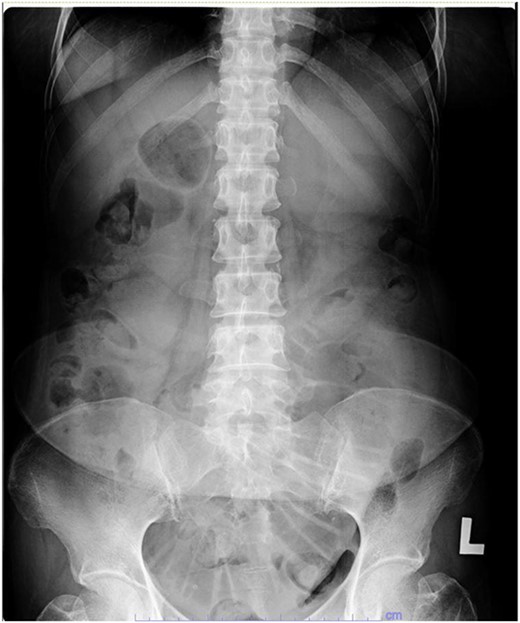

Her abdominal x-ray showed a dilated small bowel with a most likely transition point at the ileum and a collapsed large bowel (Fig. 1). Computed tomography (CT) of the abdomen showed an intussusception with the transition point at the proximal ileum with mesenteric invagination (Figs. 2 and 3).

Sagittal view of CT scan. The involved bowel loops are thickened with mesenteric invagination into the intussusception. The distal small and large bowel appears collapsed.